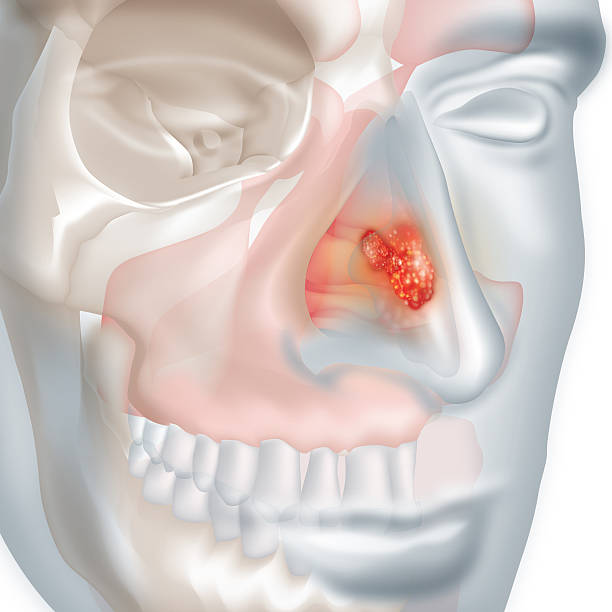

비강암의 초기 증상은 감기나 부비동염과 비슷하여 조기 발견이 어려운 암종입니다.

- 코막힘 : 한쪽 코가 반복적으로 막힘

- 비출혈(=코피) : 특별한 이유 없이 반복적으로 코피가 남

- 후각 저하 : 냄새를 잘 맡지 못함

- 안면통, 치통 : 암이 상악동이나 구강을 침범하면 치아가 흔들리고 통증이 발생

- 복시, 시력 저하, 눈 충혈, 눈 주위 부종 : 암이 시신경 압박 or 눈 주위로 퍼지면 발생

- 안면 부종, 감각 이상, 부정교합, 턱관절 움직임 장애

- 경부 종괴 : 목에 혹이 만져짐

- 청력저하

- 화농성 비루 : 고름 섞인 콧물

- 사지의 움직임 이상 : 암이 뇌신경을 압박 or 침범할 경우

비강암으로 인한 증상은 다양하고 비특이적입니다. 다만, 종괴로 인한 증상은 편측성으로 나타나는 경우가 많아, 증상이 오래 지속되거나 한쪽에만 반복적으로 나타난다면 반드시 이비인후과에 내원해 진료를 받아야 합니다.